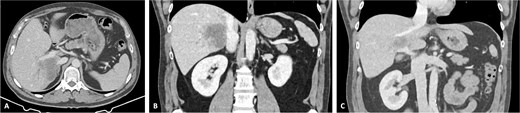

A 42-year-old asymptomatic male patient was referred with a suspicious liver mass detected on abdominal ultrasound (US). The US was made after a blood test revealed an isolated elevation of gamma-glutamyl transferase of 789 IU/l. Past and family history were unremarkable. Computed tomography (CT) scan revealed a large tumour measuring 12.6 cm occupying the right liver (Fig. 1 and Supplementary Video S1). Magnetic resonance confirmed a heterogeneous, ring-enhancing hepatic lesion with obliteration of the right hepatic vein (RHV), and invasion of the middle hepatic vein (MHV), PV, and the retrohepatic portion of the IVC. No metastatic lesions were present. Tumour markers and endoscopic exams revealed no alterations.

CT scan of the intrahepatic cholangiocarcinoma before chemotherapy. (A) Axial CT scan of the intrahepatic cholangiocarcinoma centred in liver segments 5, 7, and 8, with extension to segment 1 and invasion of the PV and IVC; (B) coronal CT scan view of the vascular relation between the cholangiocarcinoma and the IVC; and (C) vascular invasion of the PV.